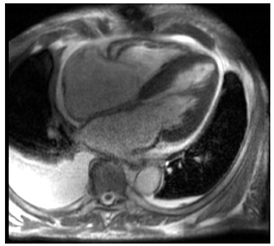

| Cardiac Structure and Function |

| ![]() |